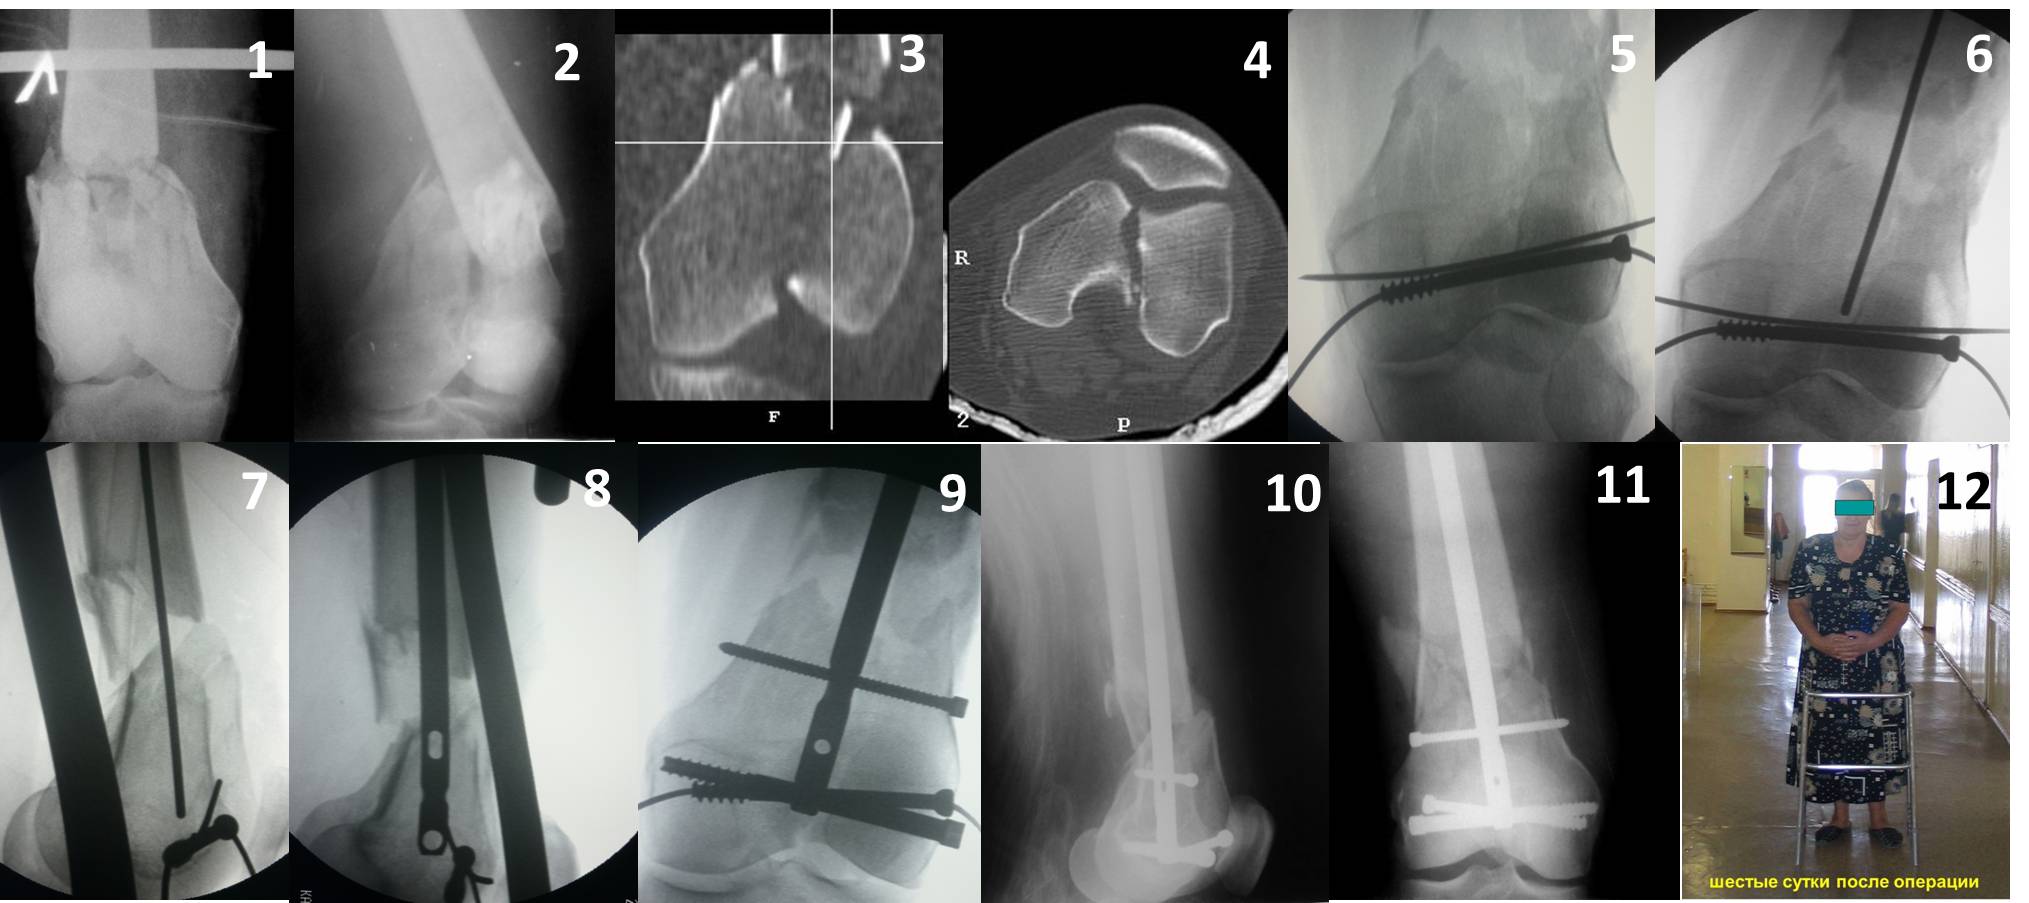

Ответ на эту часть Вашего поста – вложенный файл. Больная оперирована неделю назад по поводу открытого перелома дистального эпиметафиза бедренной кости. После операции она идёт в рентгенкабинет для выполнения послеоперационной контрольной рентгенографии, представленной на слайдах 10 и 11. Узнав, почему её фотографируют, просила передать Вам, Антон, привет.

Антеградное штифтование не очень годится при переломах типа C3, когда есть многооскольчатость именно суставной поверхности. А при переломах типа C1 и С2, т.е. и в обсуждаемом случае тоже, он как раз вполне оптимален. На межфрагментарную компрессию как-то не приходилось так драматически полагаться при интрамедуллярном остеосинтезе, результаты хорошие без нее были.

В этой терминологии мы, получается, создавали компрессию встречными спицами с упорами или reduction clamps, а потом вполне обходились запирающими винтами как позиционными. Бывает, проводим 1-2 спонгиозных винта 6,5-8 мм - вот они вполне компрессирующие.

И уже лет шесть мы используем возможность ввести в дистальное овальное отверстие 3 винта, которые именно запираются в этом отверстии, не люфтят, а обеспечивают угловую стабильность - см картинку.

Получается и стабильно, и очень дистально, нижний край отверстия в 3 мм от дистального конца гвоздя.

В приложении пример недавней операции, C3, открытая репозиция, фиксация мыщелков спицами и винтами, ретроградный синтез большеберцовым гвоздем 10,5 мм диаметром, винты 5 мм.